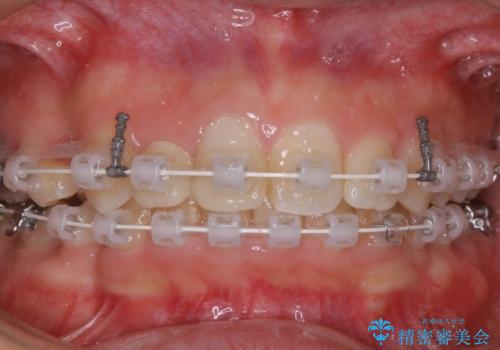

- 矯正装置

- ワイヤー矯正 審美装置